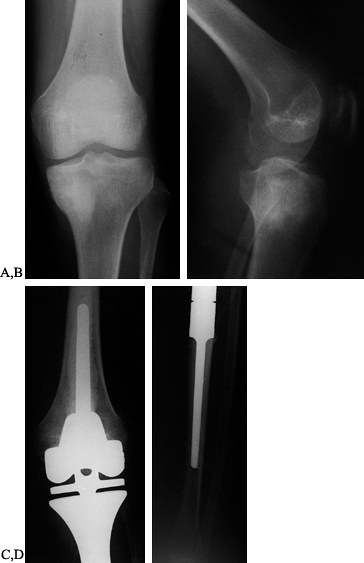

|

Figure 126.10. A: AP radiograph of the knee and proximal tibia from a 15-year-old boy. An osteosarcoma involves the upper tibia. B: Lateral radiograph of tibial osteosarcoma. C:

AP radiograph after resection of the upper tibia (intra-articular) and allograft arthrodesis. Note the intramedullary rod and screws for fixation. D: Lateral radiograph showing fusion of the knee. |